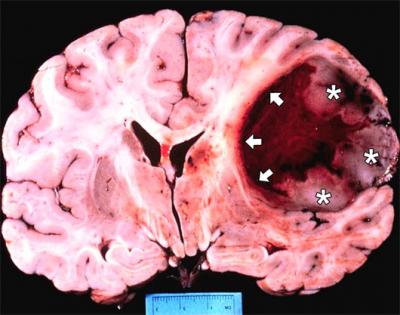

Các nhà khoa học Italy cùng các đồng nghiệp Canada đã tìm ra hai protein được cho là nguyên nhân tạo ra các khối u ở não, mở hướng đi mới trong việc tìm kiếm giải pháp chữa căn bệnh mà y học hiện vẫn bó tay. Chi tiết »